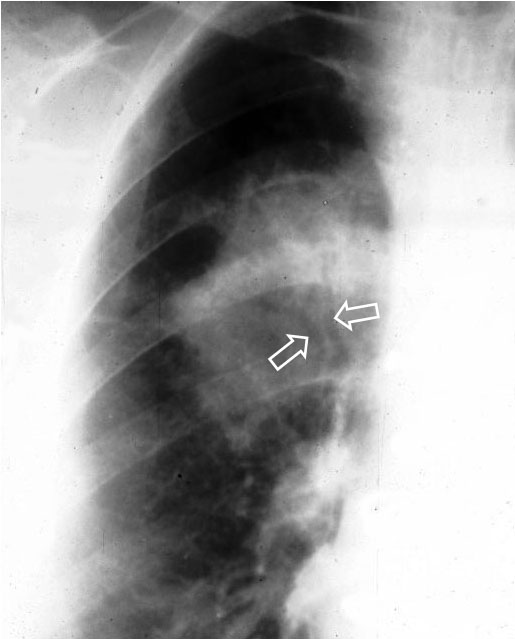

SIGNO DE LA CISURA ABOMBADA O DE LA HINCHAZÓN DEL LÓBULO

Este es un signo poco útil en la actualidad. Es visible en la radiografía de frente de tórax y se presenta como una condensación alveolar que se asocia a un abombamiento inferior de la cisura adyacente (flecha). Este signo, descrito inicialmente como característico de la neumonía por Klebsiella (neumonía de Friedlander), ha sido visto en otras entidades: neumonía por neumococo, H. influenzae, tuberculosis, absceso, neumonitis obstructiva, e incluso en el carcinoma bronquioalveolar.